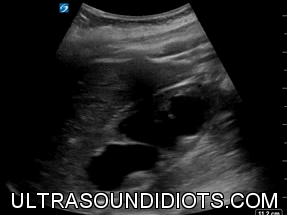

SEVERE HYDRONEPHROSIS

ANIMATION